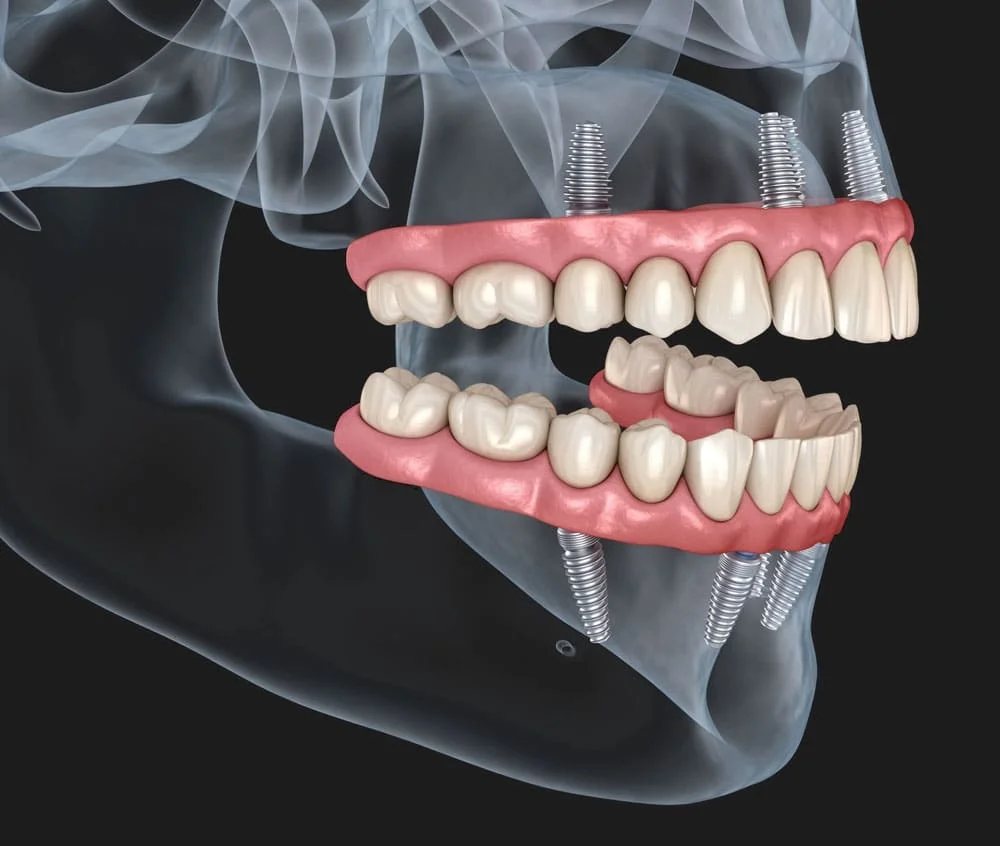

All-on-4 implant tedavisi, tüm dişlerinizi tek seans içerisinde çıkartılıp yerine 4 adet implant üzerine sabitlenen bir köprü ile değiştirmektir. Bu tedavi yöntemi, diş eksiklikleri olan kişilere daha hızlı ve daha kolay bir diş restorasyonu sağlar.

All-on-4 implant tedavisi, bir cerrahi işlemle yapılır. Tedavi sırasında, öncelikle diş etleri kaldırılır ve dişler çekilir. Sonrasında, implantlar çene kemiğine yerleştirilir ve geçici bir köprü takılır. Yerleştirilen implantlar iyileşme sürecinde kemikle kaynaşır ve kalıcı köprü yerleştirilir.

All-on-4 implant tedavisi, uzun vadede en etkili çözümlerden biridir. İmplantlar doğru bakımla ömür boyu kullanılabilir ve kalıcı bir köprü ile birlikte normal dişler gibi kullanılabilir.